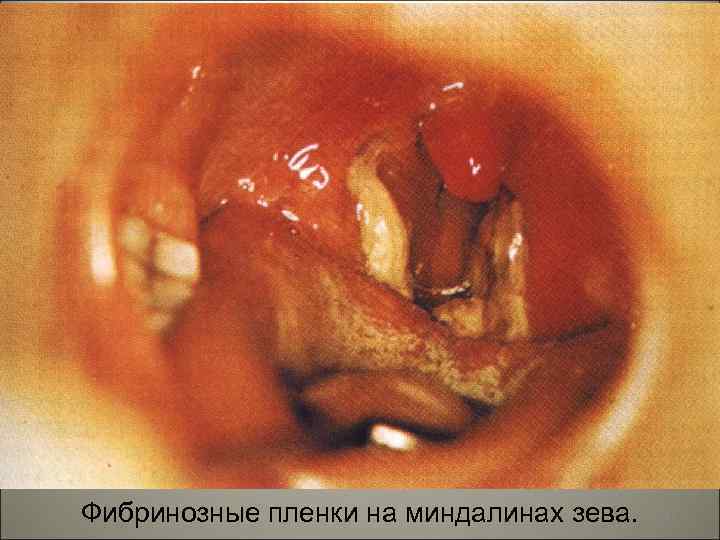

• В результате из сосудов выходит жидкая часть крови, богатая белком. Содержащийся в ней фибриноген при контакте с некротизированной тканью превращается в фибрин, образуя фибринозную пленку. На участках, покрытых многослойным эпителием (зев, глотка), возникает дифтеритическое воспаление, на слизистых оболочках, покрытых однослойным цилиндpичecким эпителием (гортань, трахея, бронхи), развивается крупозное воспаление. 114

• Клинически выделяют две основные формы — дифтерию зева и дифтерию гортани. При дифтерии зева местные изменения наблюдаются в миндалинах — ангина. Типично фибринозное воспаление миндалин с переходом фибринозных плёнок на дужки и мягкое нёбо. Плёнки плотно связаны со слизистой оболочкой, долго не отторгаются, что способствует интоксикации. Лимфатические узлы шеи увеличены за счёт некрозов и отёка, который может распространяться на всю шею и грудь. 115

Фибринозные пленки на миндалинах зева. 117